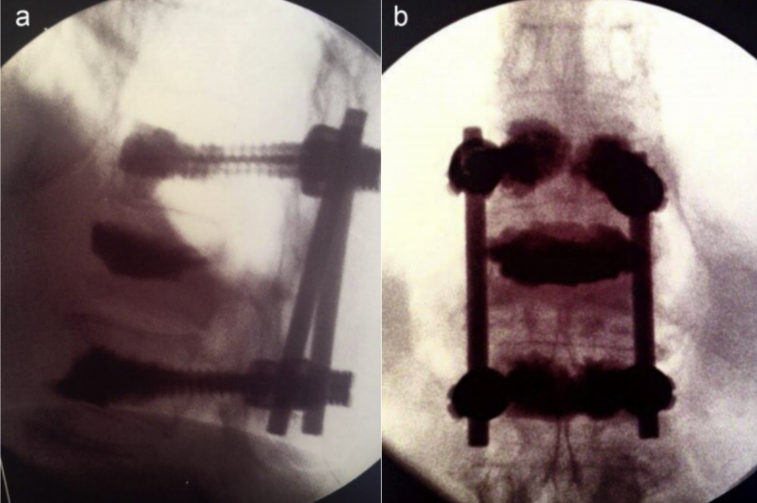

开放手术治疗

对有脊髓及神经压迫症状和体征、严重后凸畸形、需行截骨矫形以及不适合行微创手术的不稳定椎体骨折患者,可考虑行手术治疗。

为提高骨质疏松症患者内固定的稳定性,可选用特殊设计的螺钉,如加长加粗的螺钉、可膨胀螺钉或者带涂层螺钉,提高螺钉的抗拔出力;

采用特殊的置钉技术,如双皮质固定技术、皮质骨轨迹技术增强螺钉的稳定性;

延长固定节段或者使用多点固定,如椎板钩、椎板下钢丝辅助椎弓根螺钉固定可增加内固定强度;

在椎弓根螺钉周围局部注射骨水泥也可有效防止螺钉拔出,但应注意骨水泥渗漏风险和翻修困难等问题。